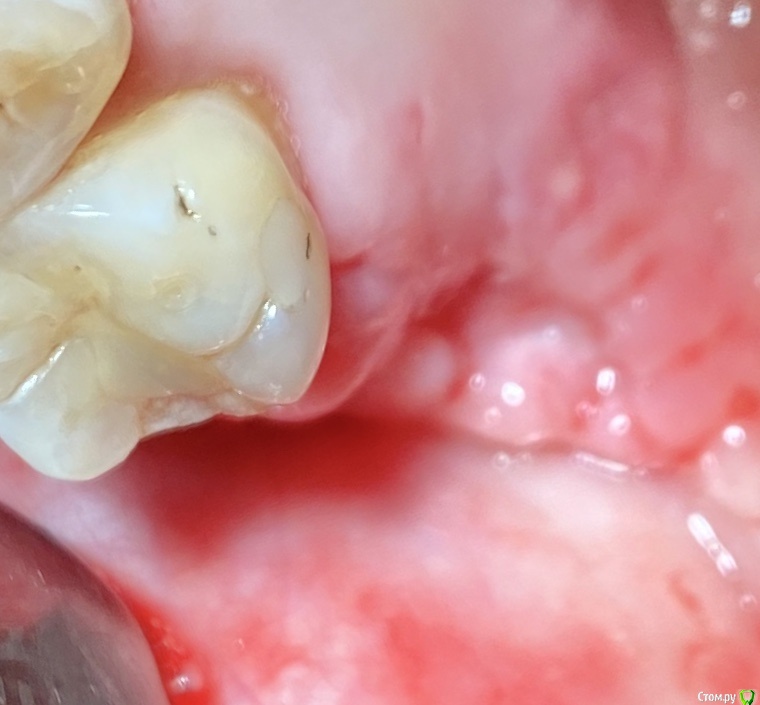

колесников Опубликовано 27 сентября, 2020 Поделиться Опубликовано 27 сентября, 2020 Вид через 2 недели Ссылка на комментарий